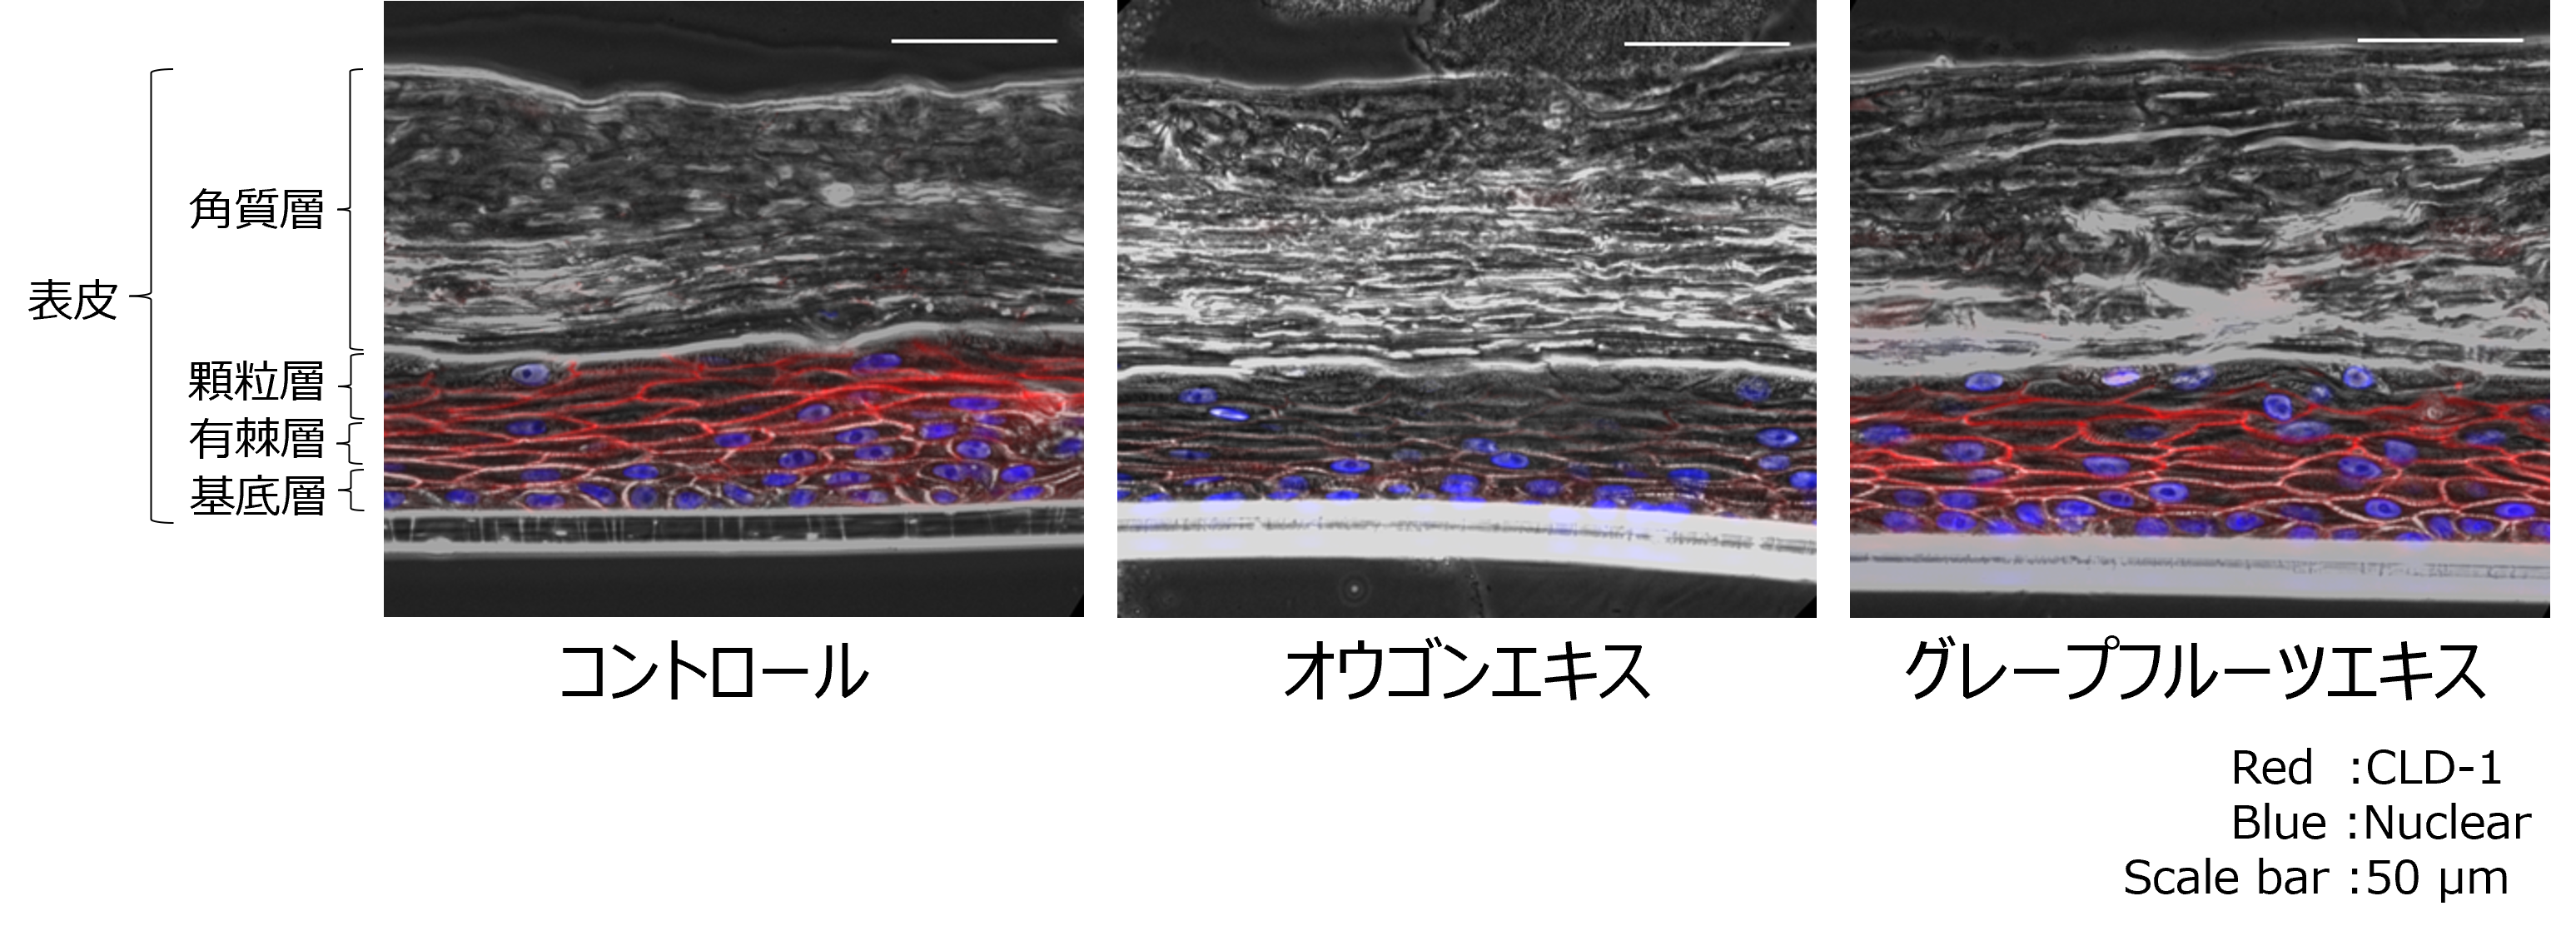

共同研究では、薬剤中の機能性成分の皮膚、毛包への浸透性を向上させる化合物、皮膚中の水分や有用成分の保持力を高める化合物の探索を行いました。タンパク質‐化合物間相互作用の類似性検索にてTJを制御するフラボノイドの探索を行い、候補成分を絞り込み、細胞を用いた機能性確認試験にて、バイカリンおよびバイカレインによるTJの緩和作用、ナリンギンおよびナリンゲニンによるTJの強化作用を確認しました。また、ヒト三次元培養表皮モデル(※2)を用いた試験では、バイカリンを含有するオウゴンエキスによるTJの緩和作用、ナリンギンを含有するグレープフルーツエキスによるTJの強化作用を確認しました(図1)。これらの検討により、ヒト頭皮におけるTJの緩和および強化作用を示す成分の機能性を応用することで、地肌や髪への薬剤の機能性効果を高めること、皮膚中の水分や有用成分の保持力を高めることが期待されます。本研究成果は、日本顕微鏡学会第79回学術講演会(2023年6月26~28日開催)にてポスター発表いたしました。また、TJ緩和および強化成分を用いた頭皮用化粧料に関して、特許(特許第7285504号 頭皮状態改善剤及びそれを含有する化粧料)を取得しました。

図1:細胞を接着しているTJの機能性成分添加による緩和と強化の働き